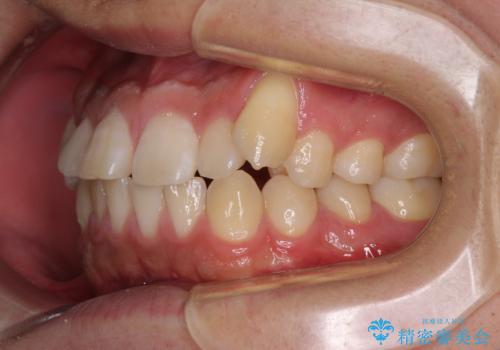

- 八重歯と前歯の隙間を気にして来院された患者様です。

八重歯の改善のため、奥歯を後方に移動させていくこととし、患者様と相談の上、ワイヤー装置にて矯正治療を行うこととしました。